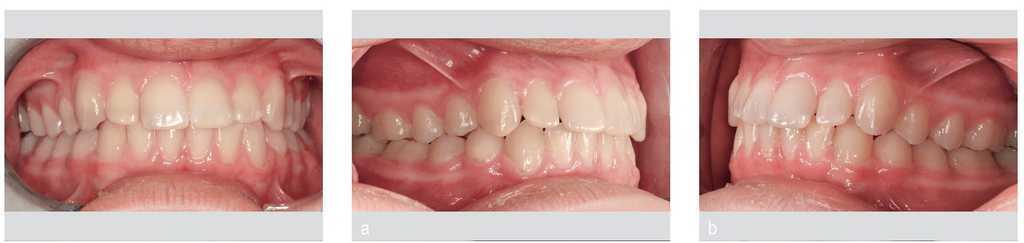

Figuras 13 y 14. Situación después de retirar la aparatología multibandas.

Una vez finalizada la parte activa del tratamiento, se confeccionó una férula de retención para el maxilar. Está previsto mejorar la estética del sector anterior con carillas. En la mandíbula se colocó un retenedor lingual fijo (fig. 23).

Figura 23. Aparatología retirada, dispositivos de retención en el maxilar y la mandíbula.